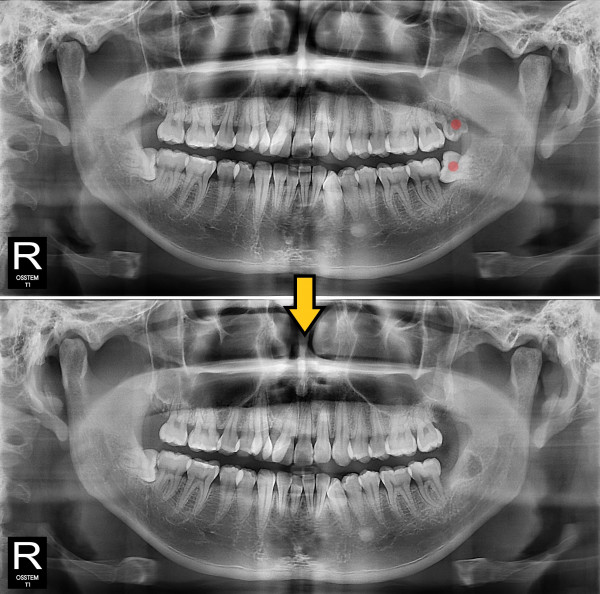

사랑니발치 부분 매복 사랑니

ae27575af29d49719312fde5a1f0cca6_1764401746_6609.jpg